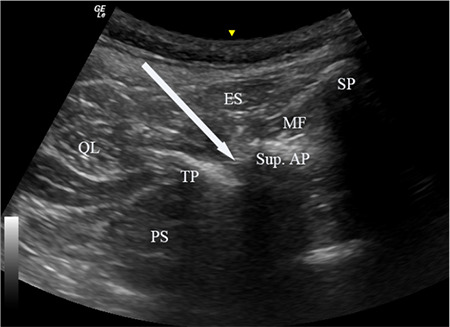

Abstract Image